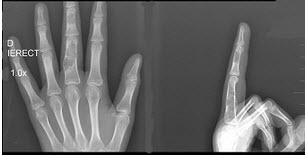

195、单项选择题

男,15岁,左侧中指局部肿胀,无压痛,关节活动无明显异常,结合图像,最可能诊断是()

A.骨质疏松

B.内生软骨瘤

C.骨巨细胞瘤

D.骨囊肿

E.动脉瘤样骨囊肿